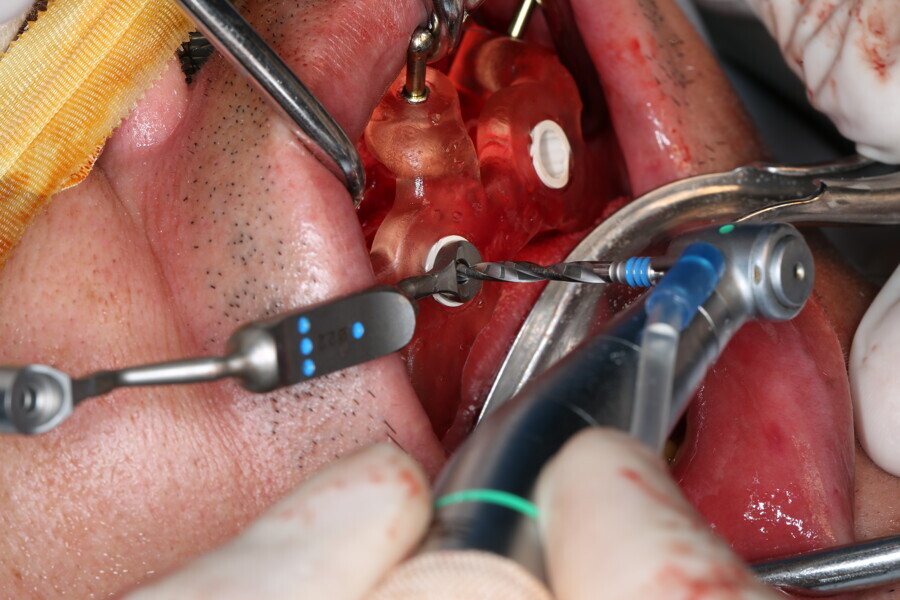

Compromised maxillary dentition treated with Straumann Pro Arch and a digital workflow